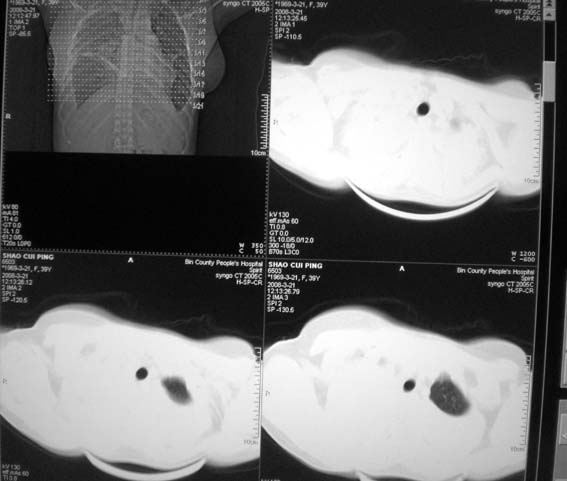

以下是引用zsl6918在2008-3-21 21:41:00的发言:[br]胸腔积液,心包积液,明确性质有难度。常规思路考虑结核性,建议抽液化验明确。

以下是引用卜一在2008-3-22 1:48:00的发言:[br][br] [br] 大量胸腔积液伴肺组织膨胀不全+心包积液。建议行纤支镜! [br] [br]

以下是引用随光逐影在2008-3-21 23:13:00的发言:[br]1)右肺中叶及左肺上叶舌段感染性病变。2)右肺中叶周围型肺癌待排。3)双侧胸腔积液并双下肺部分肺组织膨胀不全。4)心包积液。

以下是引用拾荒者在2008-3-22 21:21:00的发言:[br]胸腔积液、心包积液,双下肺膨胀不全,建议穿刺细胞学检查或抽液后进一步ct检查。